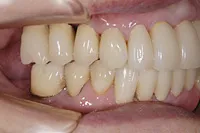

■治療前:上下顎 義歯での食事に満足されていない

■治療後:上下顎 複数本のインプラントを使い固定式で治療

| 主訴 | 現在義歯を使用しているが、しっかりと咬んでなんでもおいしく食事したい |

| 治療方法 | 上下顎 複数本のインプラントを使用しての治療 |

| 治療期間 | 約1年 |

| 通院回数等 | 約20回 |

| 費用 | 約600万円(税込) |

| リスク・副作用 | 術後の腫れ・痛み |